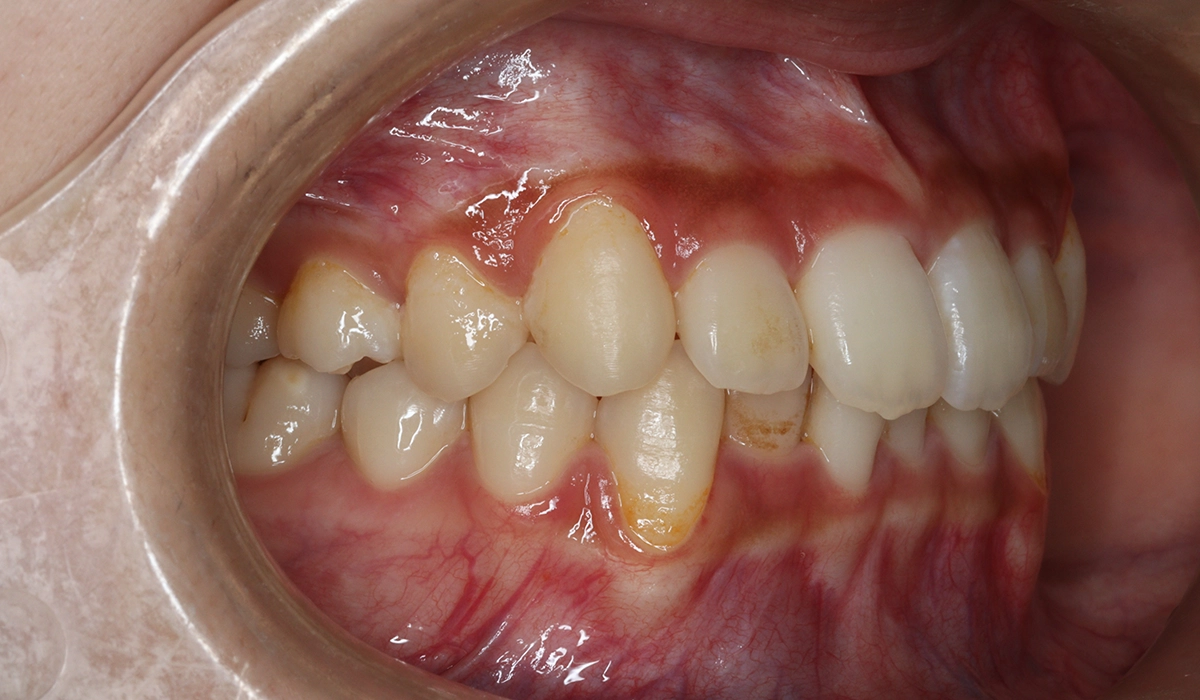

術前:右側

術後:右側